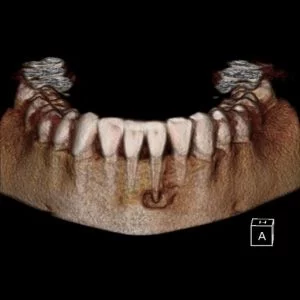

A CBCT was taken after a negative cold test indicated a necrotic tooth. When the CBCT was taken, we could clearly see that the abscess had completely perforated the labial bone at the apex of #24 and was close to doing so on #25.

As we investigated more deeply, we identified another critical piece of information that would affect our treatment plan: a second canal on #24.